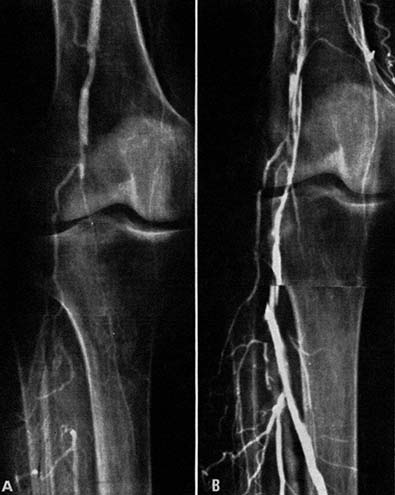

図3.膝窩動脈の完全閉塞.A.術前.B.カテーテル治療後.三分岐以下の動脈の再疎通が得られている.

当時,下肢動脈の閉塞性動脈硬化症の治療法としては,内膜剥離術,静脈グラフトなどがあったが,その適応がない場合は専ら下肢切断術が行なわれていた.ここでは下肢切断術が予定されていた9例11肢についてカテーテルによる血管拡張術を行ない,8肢で切断術を回避できた(図3).